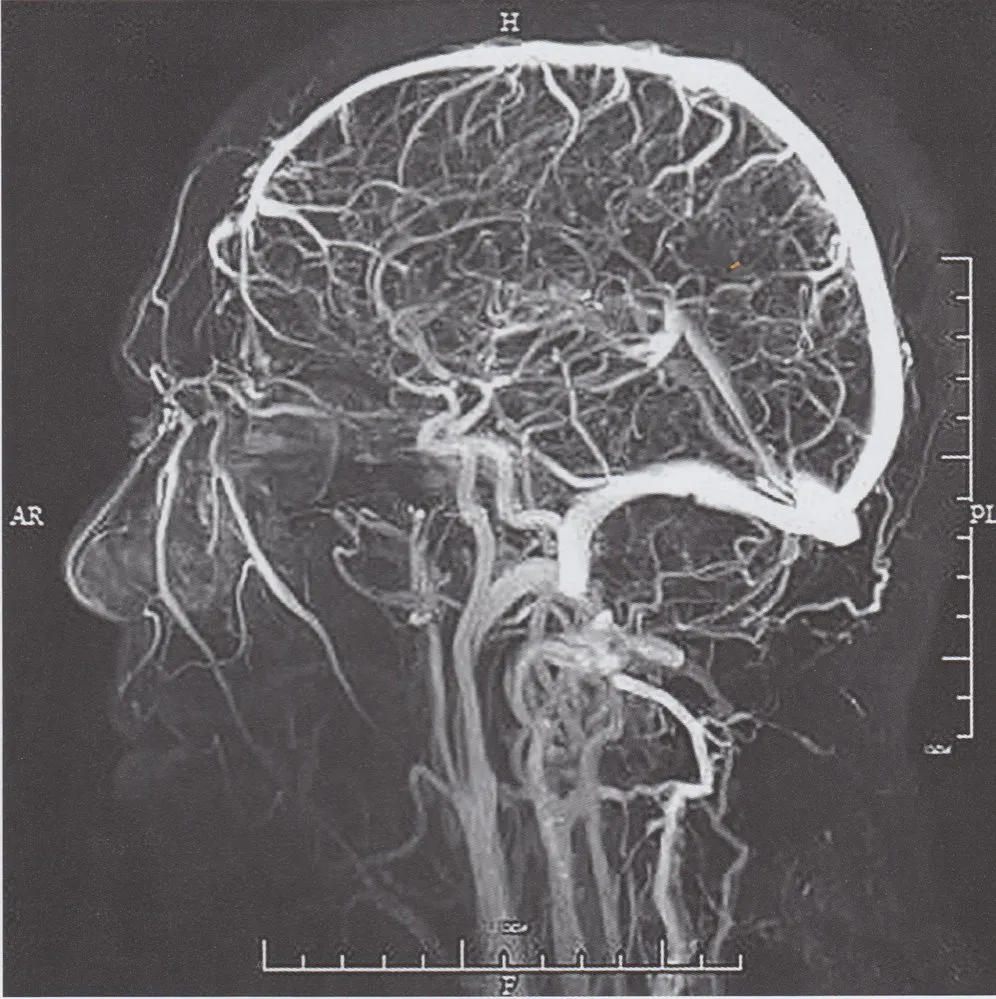

Diagnose

Thrombose des Sinus sigmoideus

Rekonstruktion einer venösen MR-Angiografie:

Bei dieser sagittalen Ansicht überlagern sich die Sinus sigmoidei beider Seiten, sodass die Thrombose nicht erkennbar ist.

1: Sinus sagittalis superior

2: Sinus transversus

3: Sinus sigmoideus

4: Sinus cavernosus

5: Sinus sagittalis inferior

6: Sinus rectus